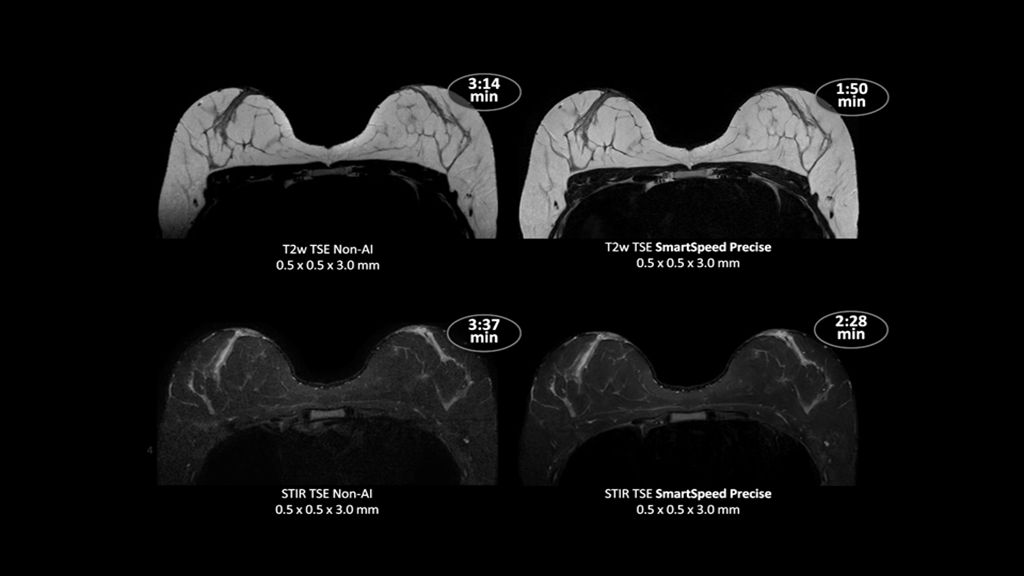

Philips - SmartSpeed Precise- Breast NMRF445C - Philips